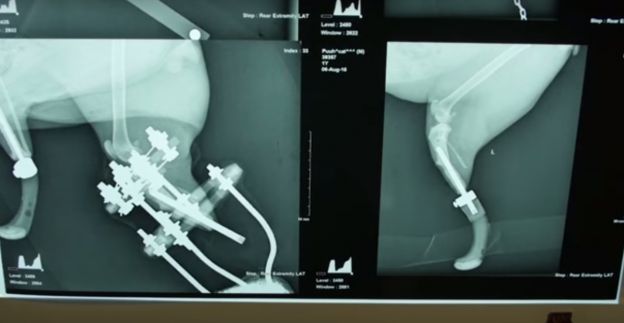

Esta radiografia é de um gatinho da Bulgária que, após sofrer um grave acidente num vilarejo local, perdeu as duas patas traseiras e ganhou próteses de titânio. Ele se tornou o primeiro “gato biônico” do país. Até então, esse tipo de cirurgia era feita apenas na Inglaterra.